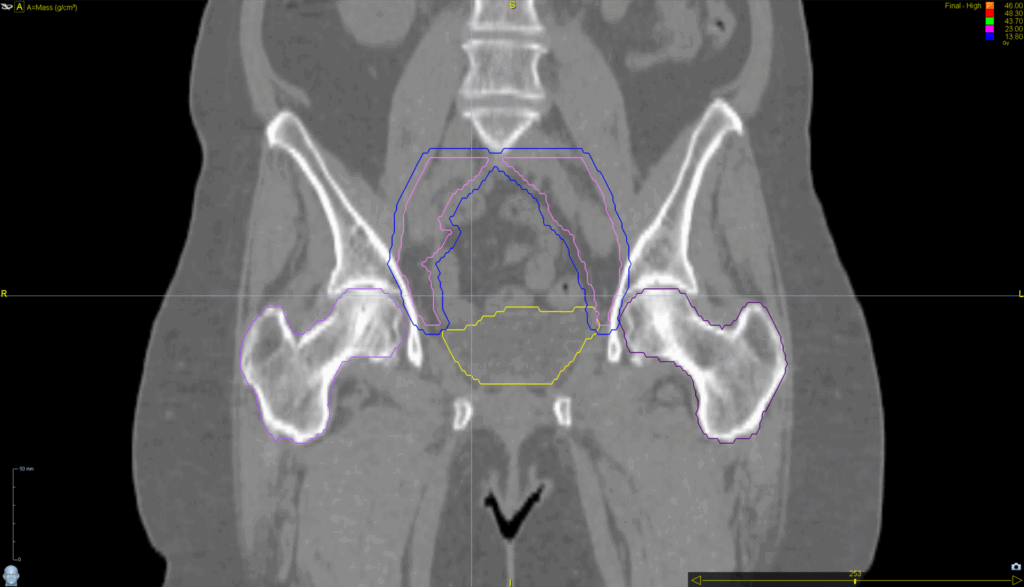

Planning CT Images

PTV(s) Volume, Length

545 cc, 15 cm